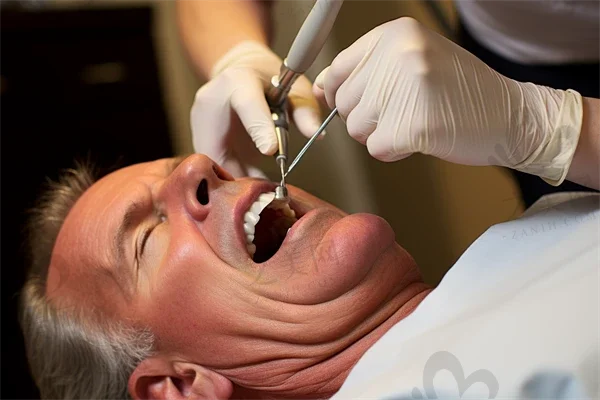

除了种植牙,医院还开展牙齿矫正、牙齿美容、牙周病治疗等多元化服务。它是时代天使、隐适美授权机构,矫正方案采用精良设计;拔牙、根管治疗可全程打“睡眠麻醉”,让患者在舒适的状态下完成治疗。

医院提供全程导医、一对一诊疗、术后回访等优质服务,注重患者的心理健康,通过心理疏导和健康教育等方式,帮助患者树立战胜疾病的信心。对于种植牙患者,医院会全程跟踪服务,从初次面诊到完成治疗,提供多方面的服务支持,包括定期复查、调整装置以及术后维护指导。